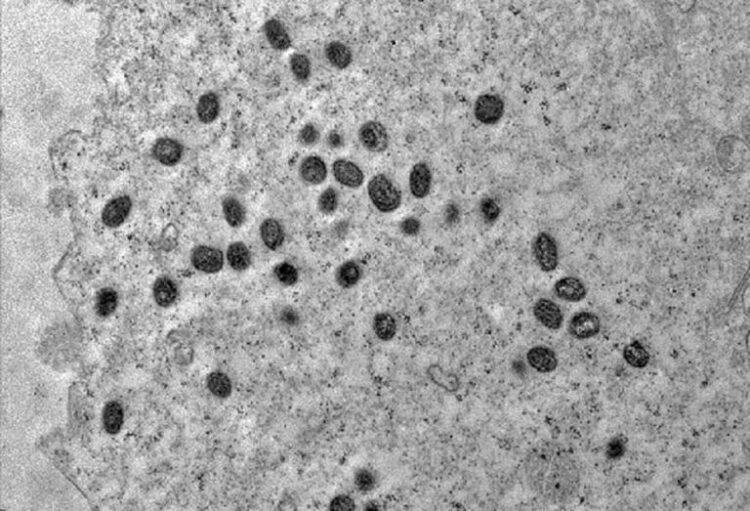

Anteriormente conhecida como varíola dos macacos, a varíola símia é uma doença infecciosa causada por um vírus transmitido aos humanos por animais infectados. O vírus também pode ser transmitido de humano para humano por meio de contato físico próximo.

Foi descoberto pela primeira vez em humanos em 1970 na República Democrática do Congo. a infecção causa febre, dores musculares e grandes lesões cutâneas semelhantes a furúnculos.